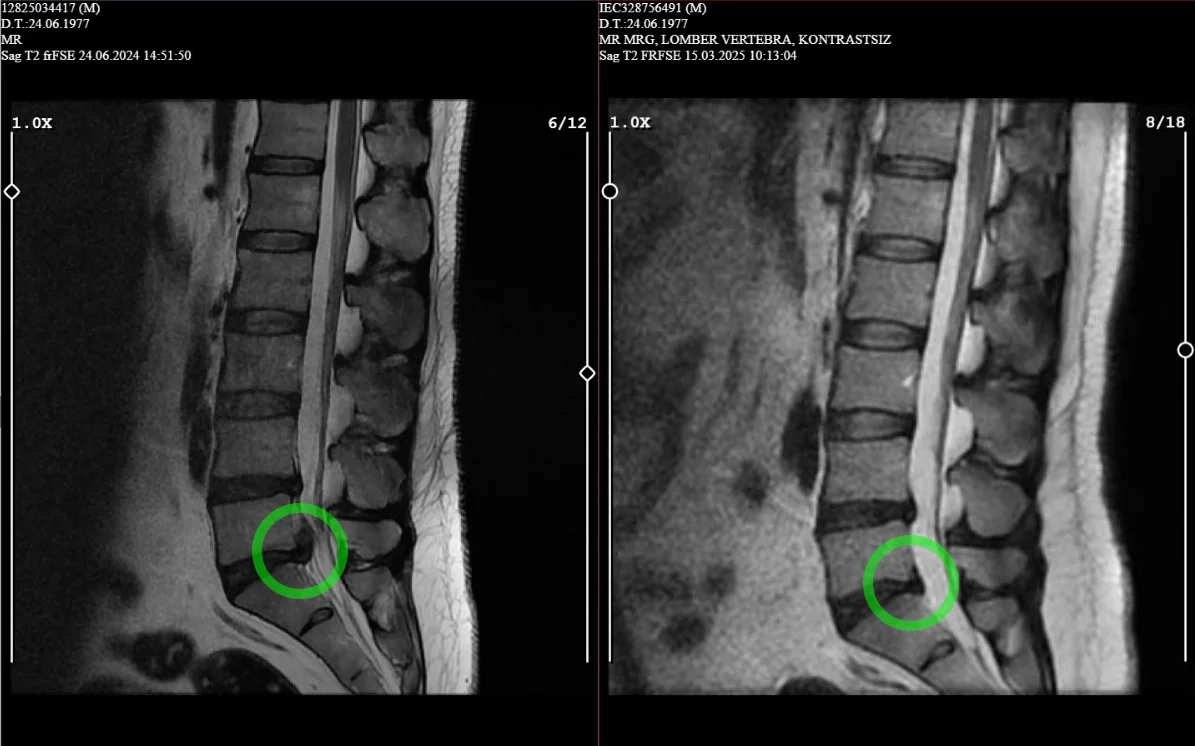

Ameliyatsız Bel Fıtığı Tedavisi

Cerrahi müdahaleye gerek kalmadan bel fıtığına etkili ve güvenli çözümler sunuyoruz